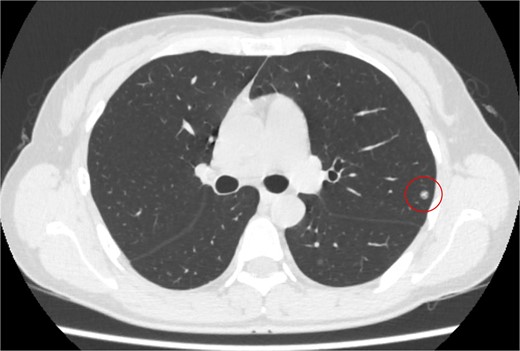

The patient was a 54-year-old woman with no history of smoking. Three years prior to being referred to our department, the patient had undergone total abdominal hysterectomy and bilateral salpingo-oophorectomy for a uterine STUMP. Six months thereafter, a single pulmonary nodule appeared in the left upper lobe (Fig. 1) and pulmonary metastasectomy was performed followed by four courses of gemcitabine-docetaxel therapy. One year thereafter, a single bulla was observed in the left lung (Fig. 2A). Subsequently, several bullae appeared and gradually developed (Fig. 2B–D); at referral, two additional pulmonary metastases were observed in the left lung (Fig. 2E and F). Because no other metastases were present, curative resection of the pulmonary metastases was planned. Additionally, we planned a bullectomy due to the lack of a reasonable explanation for bullae formation.

Computed tomography revealed a solitary pulmonary nodule (circle) in the left upper lobe 6 months after uterine surgery.